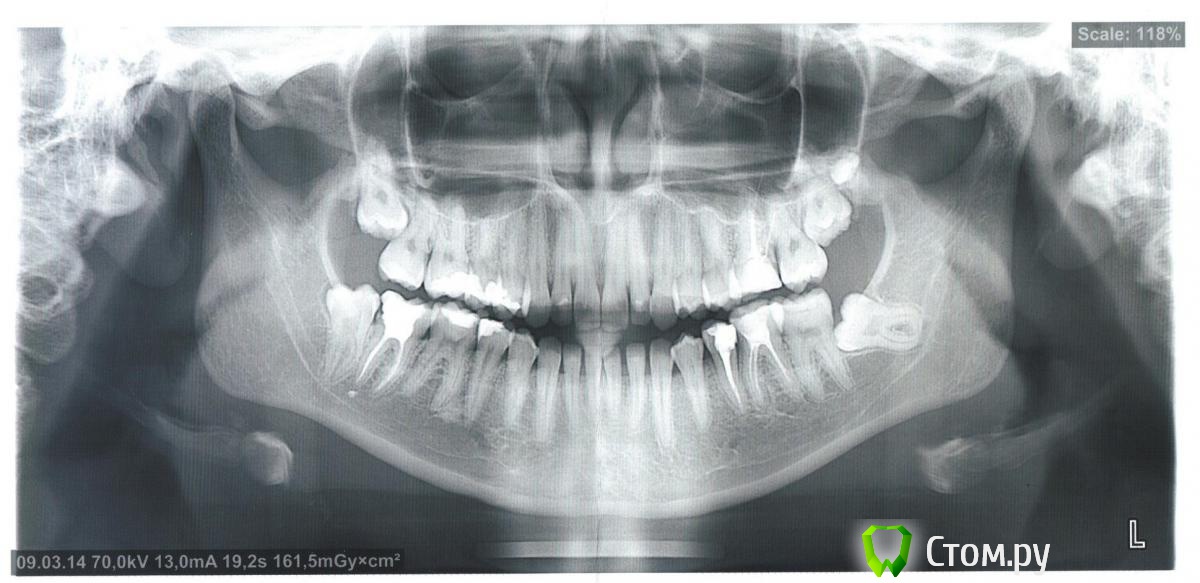

Зайка Опубликовано 20 марта, 2014 Поделиться Опубликовано 20 марта, 2014 Здравствуйте,хотела бы получить консультацию по поводу удаления восьмерок,нужно ли это делать?можно ли считать,что слева вверху ползет девятка?недавно ходила лечить зубы,десна сверху и снизу слева были немного припухши,в верхнем ряду между шестеркой и семеркой,стоматолог диагностировала карман,поэтому сняла пломбу с шестерки.Слева внизу был так же диагностирован карман,но между 5 и 6 зубом,так же была снята пломба.после снятия пломб отечность десен усилилась и десна стали очень сильно болеть,пью обезбаливающие и иногда ставлю кетонав.Стоматолог прописывала полоскания и гели,но так как у меня сахарный диабет 1 типа,гели мне не подходят,от полоскания спиртовыми растворами припухлость только усиливается,поэтому полощу лесным бальзамом с корой дуба,завариваю ромашку,а так же полощу хлоргекседином,но отечность так и не спадает.Сходила к пародонтологу,она сказала,что возможно дело в восьмерках и это они так болят,так как в целом десна выглядят неплохо и так болеть не должны.Из всех зубов мудрости чуть показалась только правая нижняя восьмерка,остальные все под десной.От пародонтолога получила направление к хирургу,консультация результатов не дала,так как врач сказал,что это не могут быть восьмерки.Справа в нижнем ряду семерка разрушина и подлежит восстановлению,есть ли смысл восстанавливать,пока там находится восьмерка?Так же прилагаю отдельные снимки верхней и нижней шестерки,так как в верхней шестерке есть подозрение на перелом в корне зуба,а в нижней шестерке воспаление в корне.Хотелось бы узнать Ваше мнение,в чем причина болей и воспаления десны и что с этим делать?нужно ли удалять восьмерки? Ссылка на комментарий

Bier Опубликовано 20 марта, 2014 Поделиться Опубликовано 20 марта, 2014 восьмерки не при чем, а вот с десной по снимку не разберешься. Хлоргексидин попробуйте фирмы Курапрокс 0,12% от него гораздо больше толку. Ссылка на комментарий

Bier Опубликовано 21 марта, 2014 Поделиться Опубликовано 21 марта, 2014 не поймешь есть ли там трещина. Скорее нет, чем да.Да, для восстановление 47з нужно удалить 48з. Ссылка на комментарий